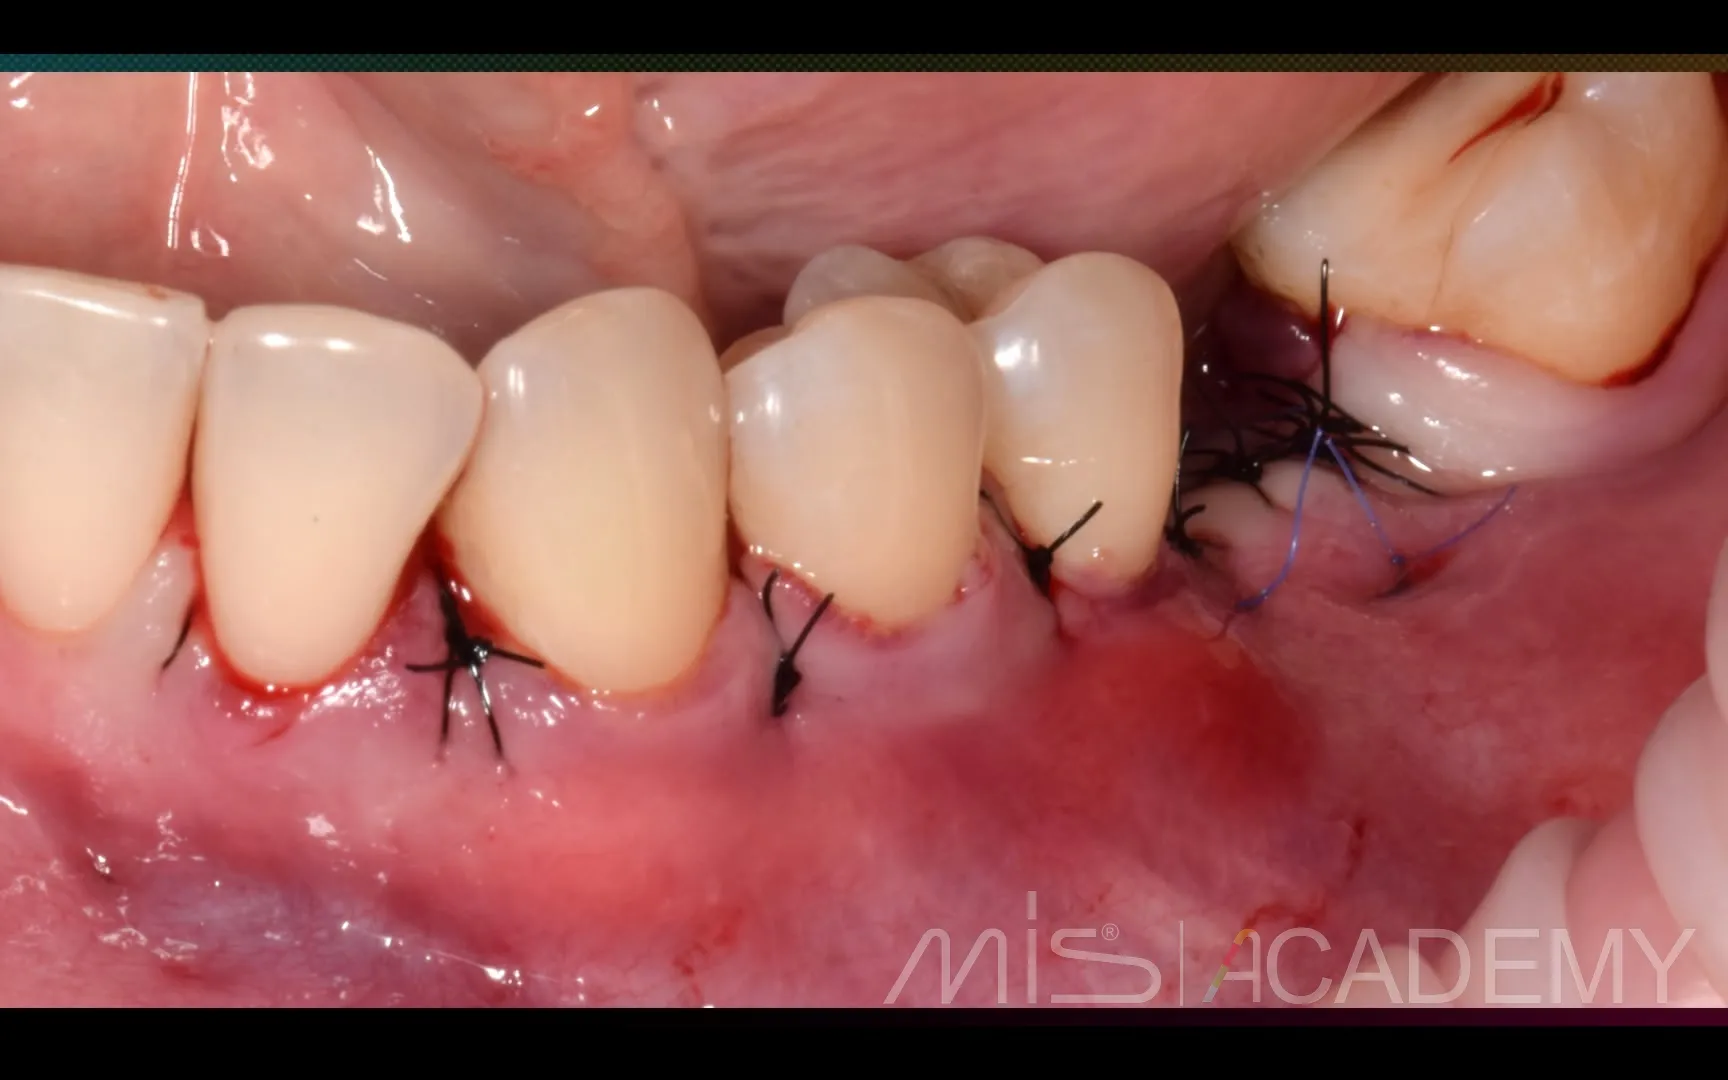

Промежуточный результат клинического кейса одномоментного закрытия рецессий и установки имплантата MIS C1 с CONNECT абатментом.